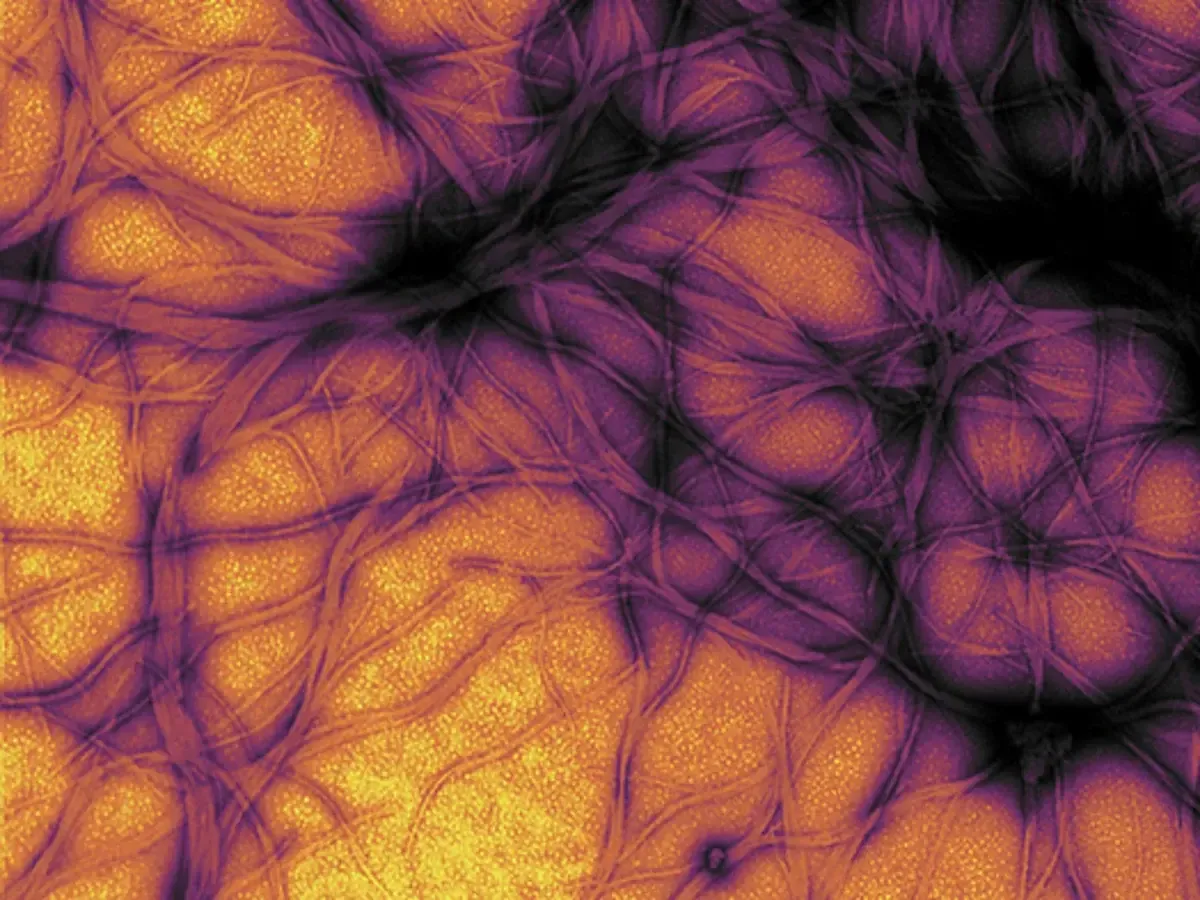

آنسفالوپاتی اسفنجیشکل انتقالپذیر (تصویر میکروسکوپی آن در تصویر نمایه گزارش است)

نمای میکروسکوپی از اسکراپی در گوسفندان